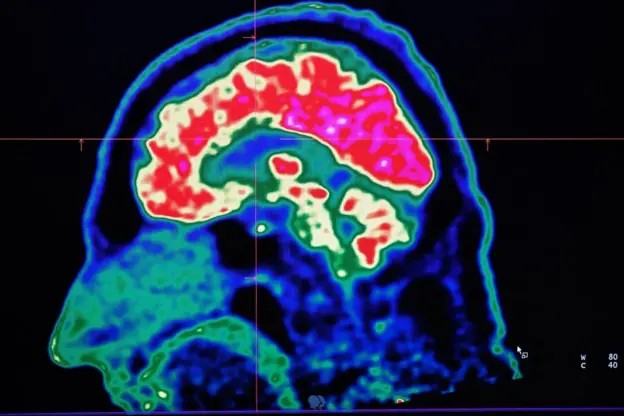

Há condições neurológicas que são agravadas pelo aumento da temperatura

A Síndrome de Dravet é apenas uma das muitas doenças neurológicas que se agravam com o aumento das temperaturas, diz Sanjay Sisodiya, da University College London, um dos pioneiros no estudo dos impactos das mudanças climáticas sobre o cérebro.

Ao se aprofundar na literatura científica, Sisodiya descobriu uma série de condições neurológicas que são agravadas pelo aumento da temperatura e da umidade, incluindo epilepsia, acidente vascular cerebral (AVC), encefalite, esclerose múltipla, enxaqueca, entre outras.

Ele também identificou que os efeitos das mudanças climáticas sobre o cérebro humano já estão se tornando visíveis.

Durante a onda de calor que atingiu a Europa em 2023, por exemplo, cerca de 7% das mortes adicionais estavam relacionadas diretamente a problemas neurológicos.

Percentuais semelhantes foram vistos durante a onda de calor no Reino Unido em 2022.